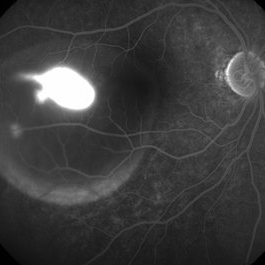

Ink Blot of CSCR

34-year-old male with right eye CSCR, FFA here shows presence of leaking site which simulates tadpole in the pond.

Condition/keywords: central serous chorioretinopathy (CSCR)